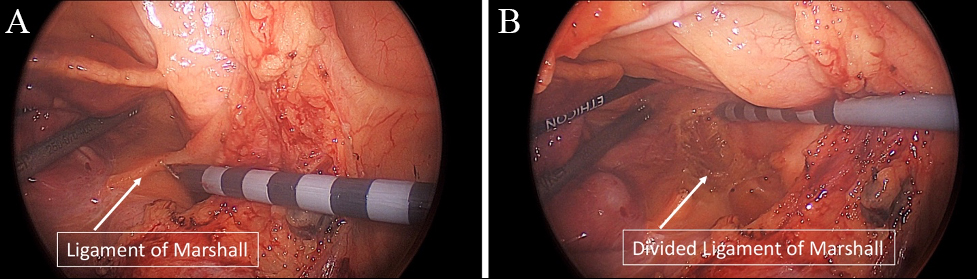

The technical aspects of the HTT Maze are less familiar to most than the Convergent hybrid approach so we have highlighted the critical steps in the following section. The HTT Maze is currently most often performed under general anesthesia in the operating room (OR) via port-access. Surgeons typically begin with left lung isolation and access the epicardium via a left pericardiotomy posterior to the left phrenic nerve bundle, similar to the LAA approach during the Convergent procedure. At this point, direct visualization of the ligament of Marshall allows for direct division via electrocautery without complication. In rare cases, a vein of Marshall is encountered, but can be readily divided with electrocautery without adverse events. The use of bipolar cautery (i.e., Ligasure or Harmonic) may also be used to divide the ligament of Marshall and provides a safe and effective method for division of this tissue without the concern for collateral thermal injury. Next, the anterior pericardial reflection between the dome of left atrium and the left pulmonary artery is developed to enhance the ability to encircle the left pulmonary veins (Fig. 6). Once completed, a lighted-tip dissector (AtriCure) is used to encircle the left pulmonary veins and then guide the safe passage of a bipolar bi-directional radiofrequency clamp (AtriCure Synergy Clamp) to encircle the left pulmonary veins on the antrum of the left atrium away from the carina of the left pulmonary veins. Prior to ablation, the pulmonary veins are tested for the presence of entrance block. If epicardial isolation of the pulmonary veins is not present than successive ablations using the Synergy clamp are performed until successful isolation is confirmed with epicardial testing. After left pulmonary vein isolation, partial interconnecting lesions from the left pulmonary vein isolation across the roof and floor are performed using radiofrequency devices (i.e., AtriCure MLP or Coolrail). The interconnecting floor lesion between the left inferior pulmonary vein and right inferior pulmonary vein can often be completed, as visualization of the right inferior pulmonary vein is accessible in most patients. The interconnecting roof lesion between the left superior pulmonary vein and the right superior pulmonary vein, however, is often incomplete due to the fat pad between the dome of the left atrium and the superior pulmonary vein. This fat pad is most often developed from the right chest and can be readily completed at that time in order to complete the interconnecting roof line. After completion of the interconnecting lesions, the coumadin ridge lesion is created with radiofrequency (i.e., MLP) from the base of the left atrial appendage to the left superior pulmonary vein. Finally, some surgeons have also incorporated either a lateral mitral isthmus (coronary sinus to the left inferior pulmonary vein) or anterior mitral isthmus lesion (left superior pulmonary vein to the mitral annulus) to complete the left sided approach. Attention is then brought to left atrial appendage, which is then sized, and ligated with an AtriClip device (Pro-Clip 2 or V-Clip) in most instances. Placement and successful ligation of the left atrial appendage is confirmed with transesophageal echocardiography. This completes the left sided approach and can be accomplished in experienced hands in approximately 30–45 minutes. The remainder of the ablations are then performed from the right chest. Again, using right lung isolation and 3 or 4 port access, the right epicardium is visualized via a right pericardiotomy anterior to the phrenic bundle. The oblique and transverse sinuses are then developed to allow for complete access across the epicardium to the left side of the heart in order to visualize the prior partial interconnecting lesions. The right pulmonary veins are then epicardially tested in a similar fashion and ablated with the Synergy clamp to achieve electrical isolation. Importantly, the interatrial groove (Waterson’s groove or Sonegards groove) is developed to again aid with placement of the Synergy clamp on the antrum of the left atrium away from the carina of the pulmonary veins (Fig. 7). Completion of the interconnecting roof and floor lesions are then accomplished with radiofrequency energy to complete the posterior wall isolation. Finally, intercaval superior vena cava and inferior vena cava lesions can be completed as well right atrial free wall “T-lesions” and lesions to the right atrial appendage. In experienced hands, the right chest lesions require approximately 30–45 minutes also. The right sided pericardium is then reapproximated to prevent right atrial herniation post-operatively.

Fig. 6.

Fig. 6.Totally thoracoscopic mobilization of the anterior pericardial reflection and division of the ligament of Marshall. (A) Ligament of Marshall (LOM) and Anterior pericardial reflection before mobilization and (B) after mobilization/ligation.